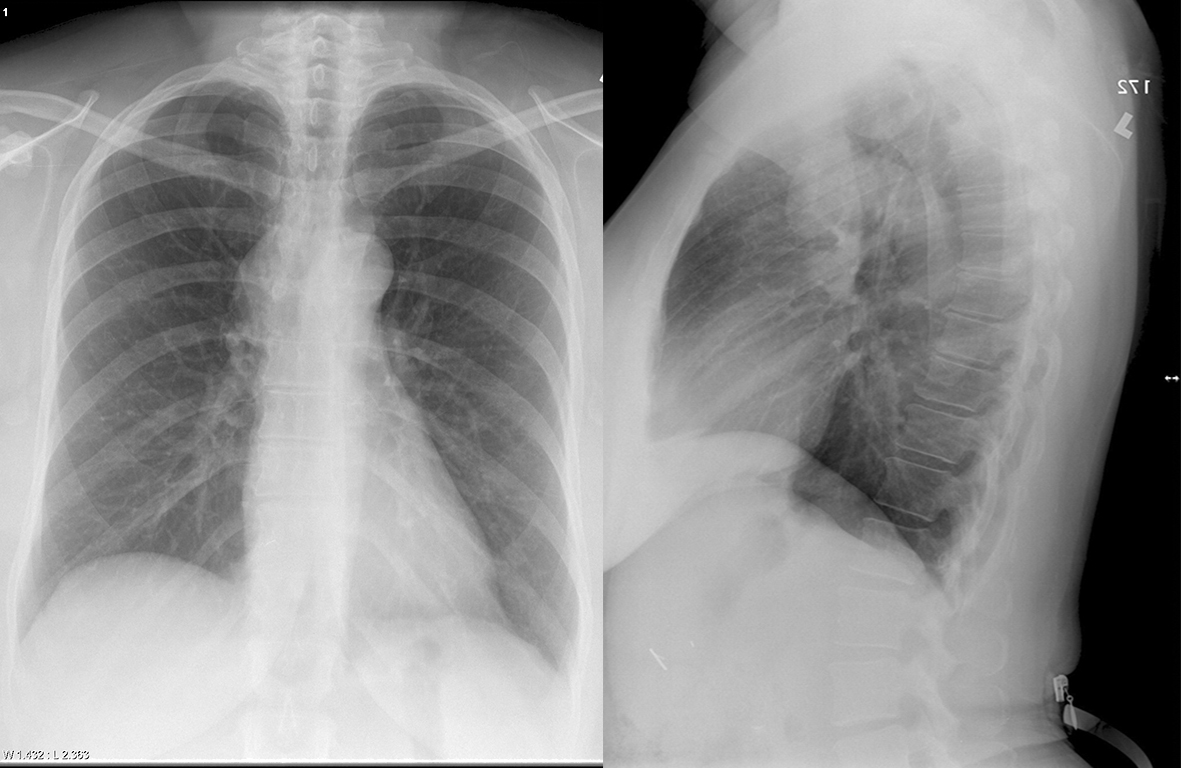

Br cyst Pa and Lat

Bronchogenic cyst